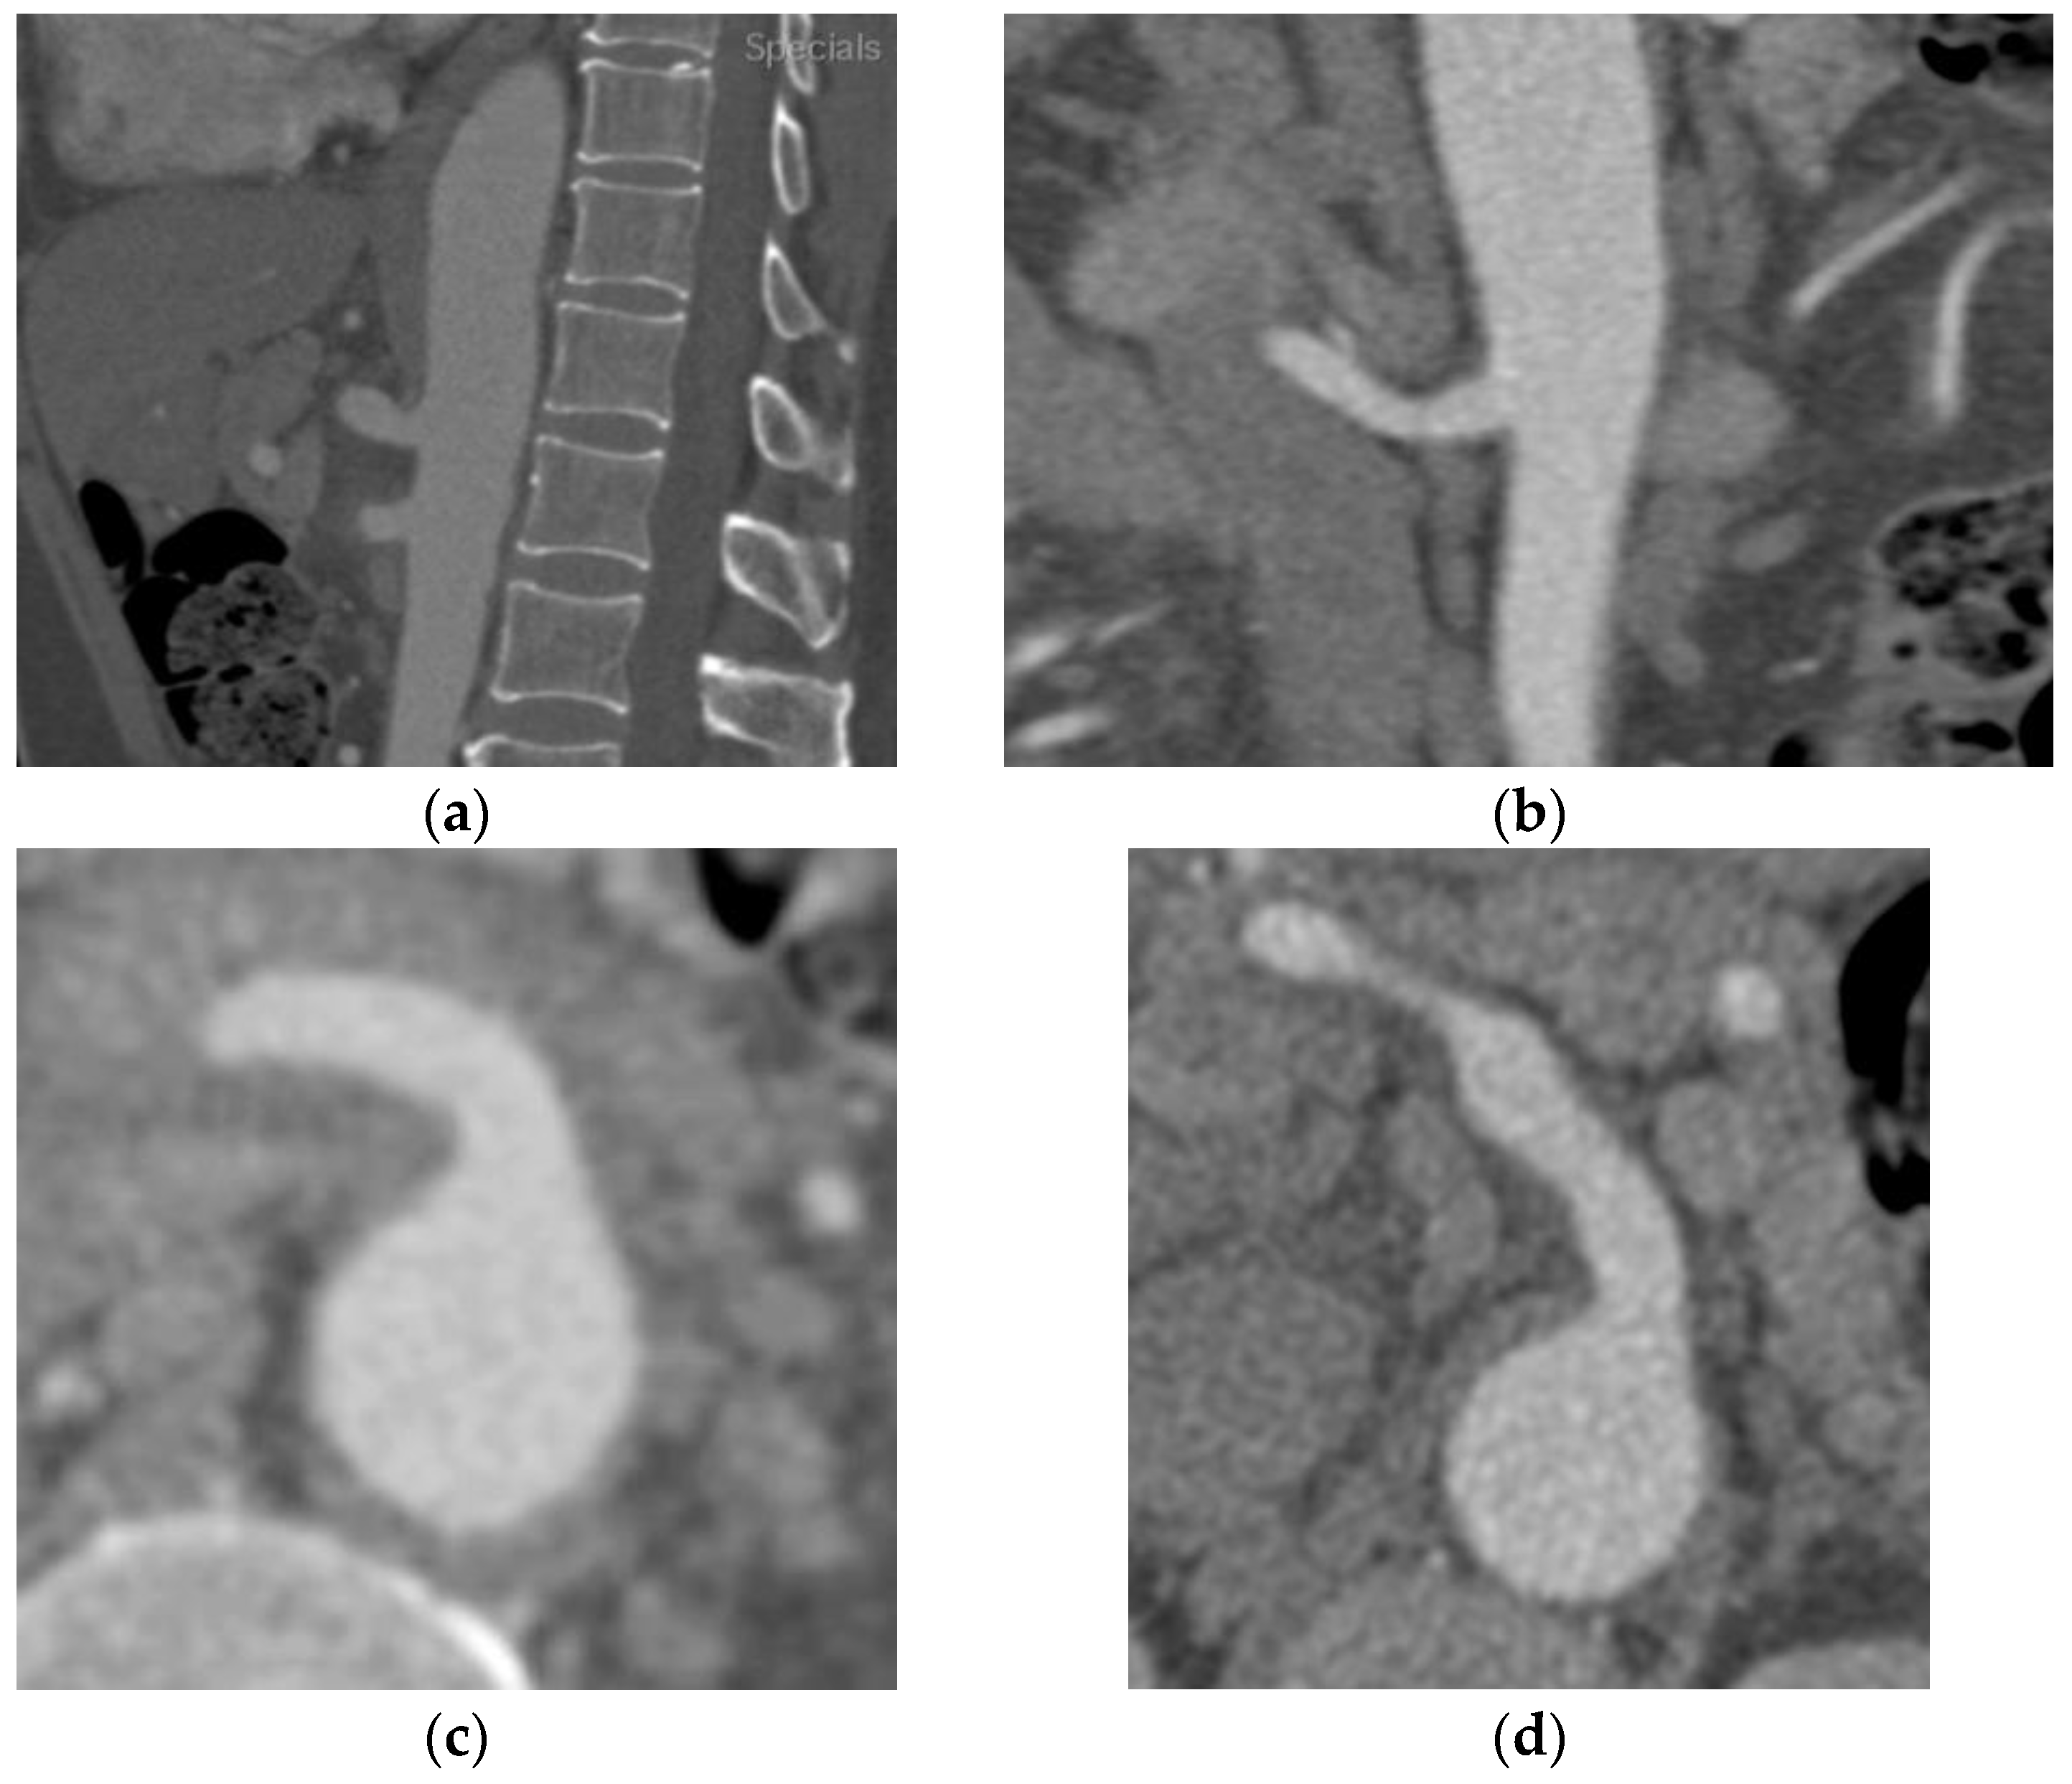

2.1. Case A